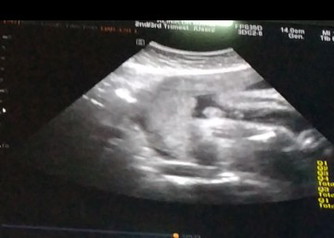

sape pandai tgk scan ni?

Sape pandai cube teka boy ke gegel???

Boboy tu nmpk birdπ

Boboy ni nmpk gayanyaa

Mcm baby boy ?

Macam boy je.

girl ni

Boy